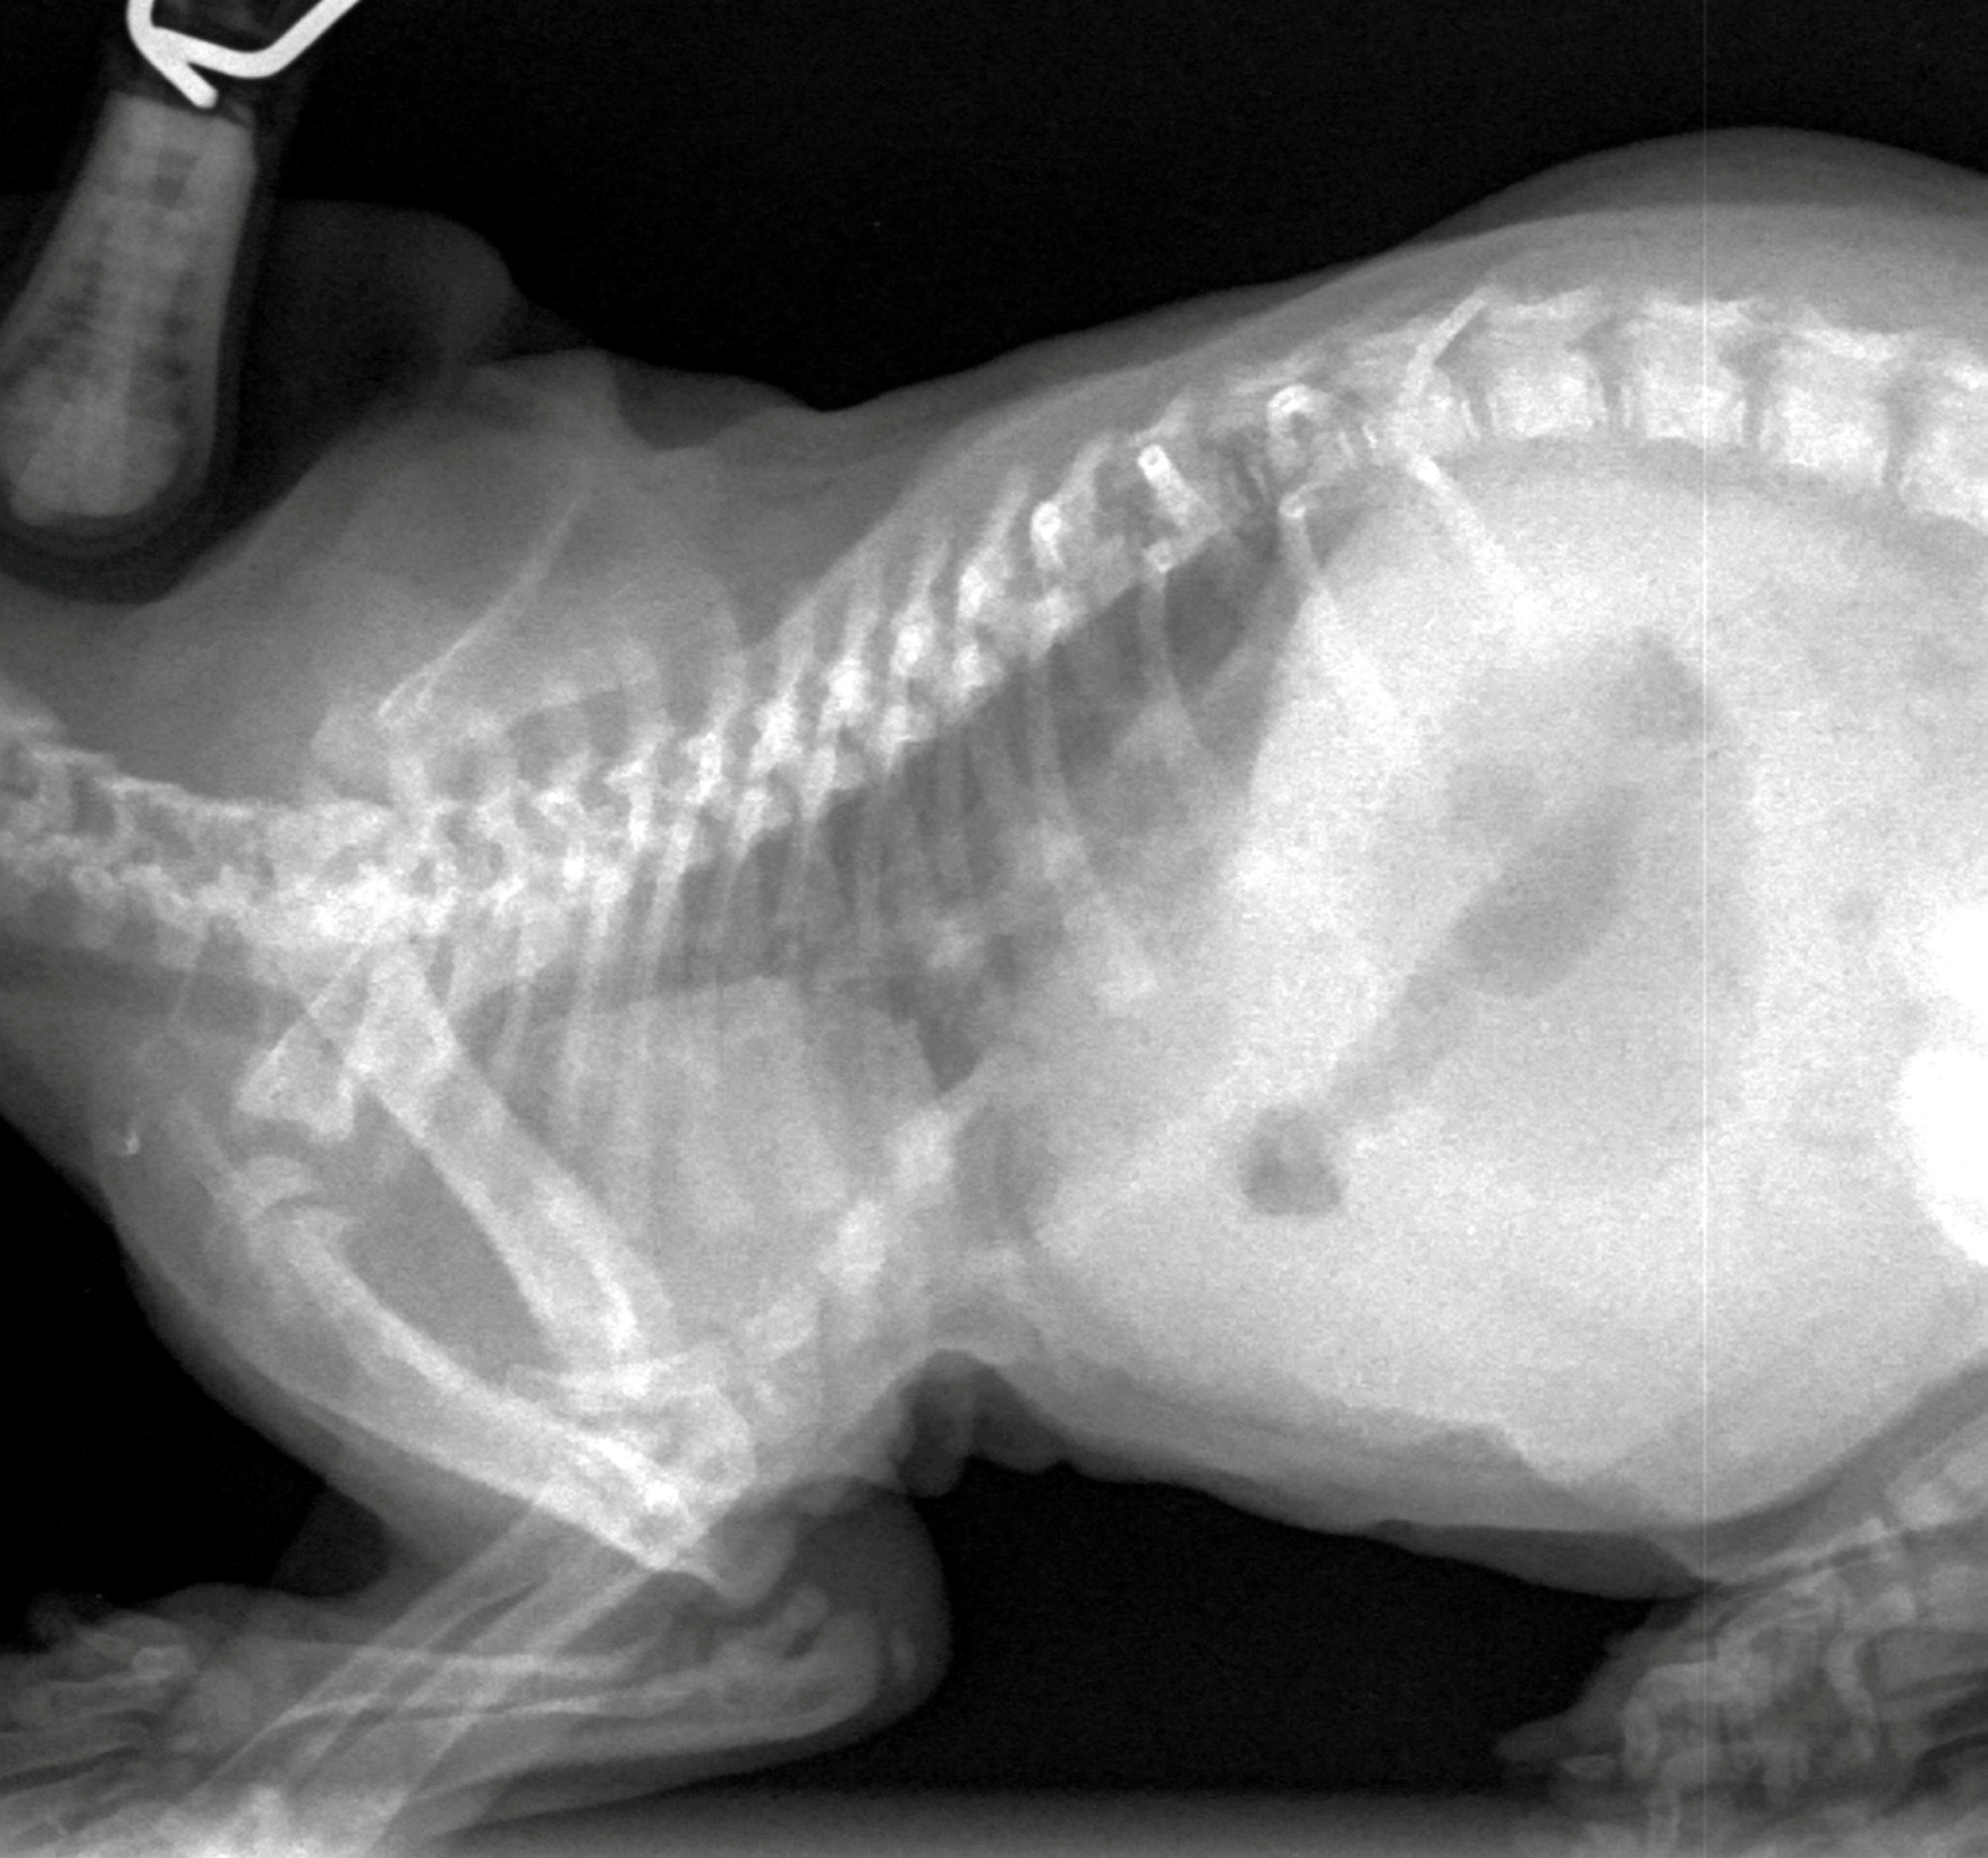

Одним из эффективных методов диагностики пневмонии у кота является рентгенографическое исследование, которое представляет собой метод динамического исследования с помощью рентгеновских лучей. В реальном времени с помощью данного аппарата ветеринар способен наблюдать за состоянием внутренних органов животного и выбирать наиболее подходящую проекцию для снимка с целью определения наличия или отсутствия воспаленных элементов в легких.

Рентген грудной клетки. Рентгеновский снимок выполняют в двух проекциях – когда животное находится в положении лежа на боку и лежа на животе.

— Кашель, ведущий клинический признак воспалительного процесса в легких, является весьма распространенным симптомом многих заболеваний у собак и кошек. Поэтому диагноз пневмония нельзя поставить только на основании результатов клинического осмотра, требуется проведение рентгенологического обследования. Учитывая данные анамнеза жизни и болезни можно выделить пациентов из группы риска, которых следует обследовать наиболее тщательно.

— Кашляющие собаки и кошки с высокой температурой, с отсутствием аппетита, безучастные к окружающему миру обязательно должны пройти рентгенологическое обследование; у многих пациентов с пневмонией лихорадка отсутствует, а у некоторых даже сохраняется нормальная активность.